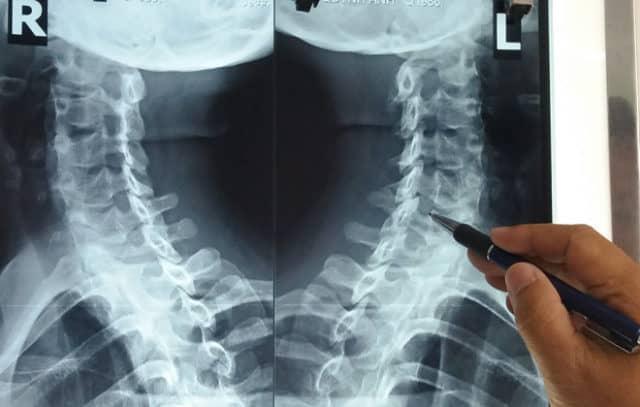

Tình trạng các đĩa đệm và đốt xương sống ở cột sống cổ bị suy thoái dần theo thời gian gọi là thoái hóa đốt sống cổ. Thoái hóa đốt sống cổ mạn tính, tiến triển chậm và có thể xảy ra ở bất kỳ vị trí nào, đặc biệt thường gặp nhất là ở vị trí C5-C6. Đây là bệnh lý vô cùng phổ biến, hơn 85% những người trên 60 tuổi mắc phải tình trạng này.

Ngoài ra, bác sĩ còn có thể thực hiện các xét nghiệm hình ảnh hoặc kiểm tra chức năng thần kinh khác để xác định chẩn đoán: